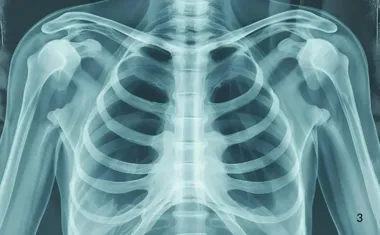

Badania diagnostyczne w torakochirurgii – kiedy potrzebna jest torakoskopia lub biopsja

Nie każda zmiana w klatce piersiowej wymaga od razu operacji. Często kluczowe jest wykonanie precyzyjnych badań diagnostycznych, takich jak torakoskopia czy mediastinoskopia. Torakochirurg ocenia obraz radiologiczny i w razie potrzeby wykonuje biopsję węzłów chłonnych śródpiersia lub innych struktur, aby potwierdzić rozpoznanie i zaplanować leczenie.

Współczesna torakochirurgia w coraz większym stopniu opiera się na technikach małoinwazyjnych – torakoskopia (VATS, video-assisted thoracoscopic surgery) pozwala zajrzeć do jamy opłucnej i płuca przez 1–3 niewielkie nacięcia o długości zwykle 1–3 cm, bez konieczności klasycznej torakotomii z szerokim rozwarciem żeber.